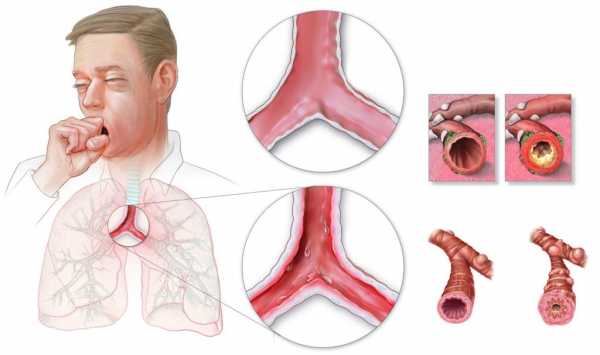

Понятием «бронхит» в медицине обозначают воспалительный процесс, возникающий в слизистой оболочке бронхов.

Бронхит может быть острым, возникшим впервые или повторяющимся не чаще раза в три года. Если же воспаление бронхов возникает чаще, говорят о хронической форме заболевания. Также бронхит бывает обструктивным и необструктивным.

При обструктивной форме возникает спазм бронхов и они перестают проводить воздух в лёгкие (фото). При необструктивной форме такого не происходит.